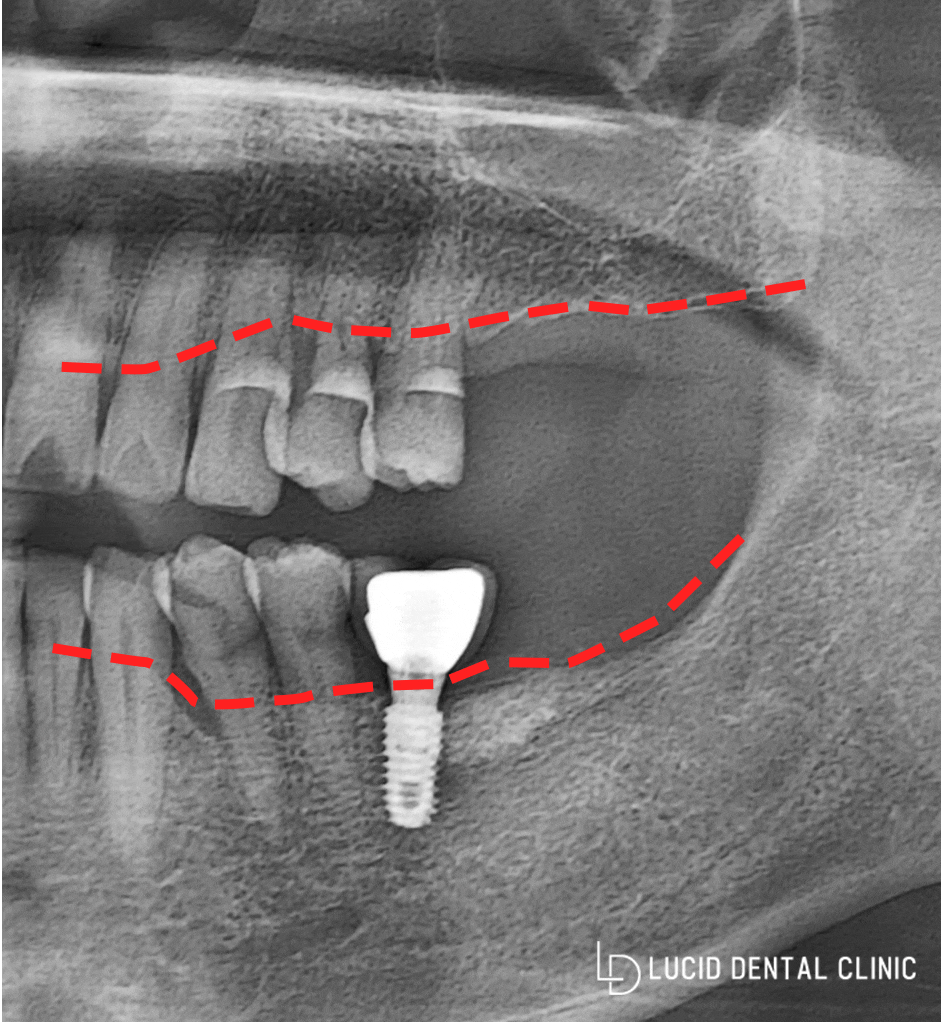

- 첫 진료 당시

처음 오셨을 때,

환자분께서 좌측 위아래 어금니가

없는 것을 확인 후

파노라마 촬영을 통해

뼈 상태는 어떠한지 확인해봤습니다.

다행히 임플란트 식립에 있어

크게 문제될만한 정도는 아니었습니다.

뼈 두께나 골질은 보철물을 심기에

적합한 기준을 갖고 있었습니다.

만약 이때 논현동 치과 를 찾아오지 않고

좀 더 오래 방치하셨다면,

뼈이식을 동반한 수술을

받으셨을 가능성이 높습니다.